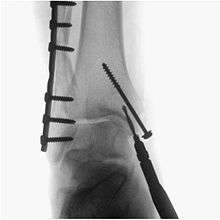

- Orthopaedic surgery to guide fracture reduction and the placement of metalwork.

- Podiatric Surgery to guide fracture reduction and in use in certain procedures that have extensive hardware.